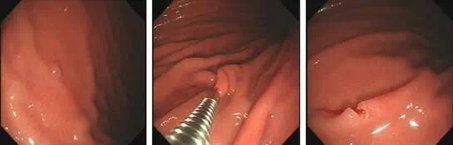

常用方案:一般较小的(直径<5mm),在行胃肠镜检查时,医生会直接用活检钳钳取。见下图:

热活检钳有什么作用【健康科普】发现胃肠息肉,到底要不要切?_https://www.jmylbn.com_新闻资讯_第4张

1. 发现息肉 2.活检钳夹住息肉 3钳除息肉